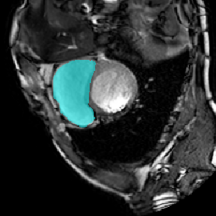

Figure 5 provides a visual representation of our model’s segmentation, indicating its superior accuracy, particularly in the right ventricle (RV) organ. While other methods display complete segmentation, our segmentation aligns more closely with the real mask.